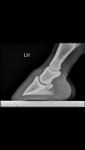

I wondered if his hypermobility might be partly responsible, and his weight comes down further back than on a horse with shorter, more upright pasterns and more stable fetlock joints. So there is more abrasion put through the heel and more of a forward slide to the foot as it lands? I have wanted to develop the heel to take the strain off the suspensories, but I’m wondering if it’s a vicious cycle in that the lax suspensories are impacting the plantar angles? X-rays show them to be flat.(I’ve put left hind photos and right hind X-ray, as they were the first I found, but they are similar)